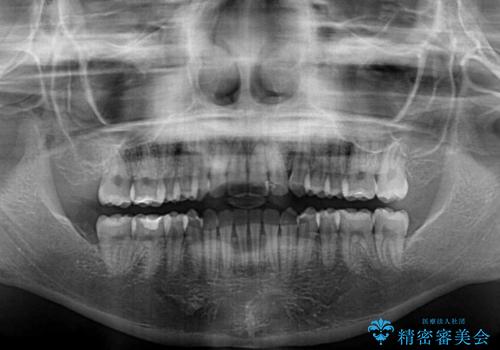

- 前歯のデコボコを気にして来院された患者様です。

マウスピース矯正のような自己管理の煩わしさがなく、早く治療を終えたいとのことで、ワイヤー装置による矯正治療を行うこととしました。

当初予定通り、1年で治療を終えることができました。

後戻り防止はマウスピースで行うため、急に自己管理が必要となるため、移動の最後をマウスピース矯正で行うことで、マウスピース非装着による後戻りリスクを回避する工夫をしています。